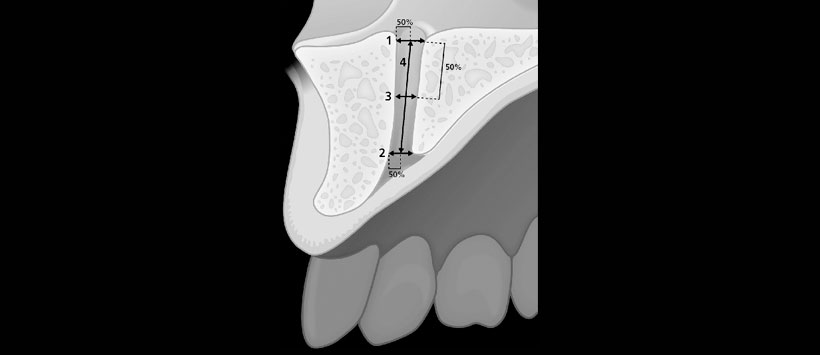

Las dimensiones del CNP, incluyendo la longitud, el ancho a la mitad y el diámetro del foramen incisal y nasal, se midieron en planos sagitales y axiales de CBCT. Además, se realizó una evaluación de los signos de abultamiento, la osteólisis apical del incisivo y su fusión con el CNP.

- Figura 1: Vista esquemática de las diferentes medidas realizadas en los planos sagitales de las imágenes CBCT (nº 1 a nº 4).